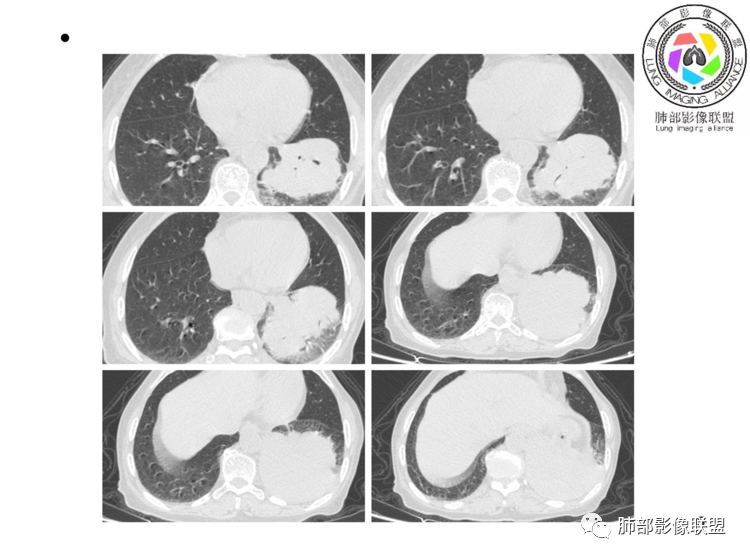

老年女性,左肺下叶软组织肿块,密度较均匀,边缘膨隆分叶,临近支气管截断,肿块内可见支气管穿行,与膈肌分界不清,增强后动脉期轻度均匀强化,静脉期呈渐进性强化,欠均匀,内血管走形如常,可见血管漂浮,整体感觉病灶偏软,考虑淋巴瘤可能大,鉴别腺癌。

患者老年女性,上腹部疼痛一周,无呼吸道症状,查体无阳性体征。血常规、尿常规、肝肾功能正常。肿瘤标志物CA125稍升高。胸部CT:左肺下叶肿块灶,边缘欠光滑,边界欠清楚,见分叶、血管集束征象,内见支气管扩张,增强中度强化,见血管漂浮征象。综合考虑恶性病变,淋巴瘤可能大,鉴别肺癌。

左肺下叶实变影,形态尚规则,外缘欠光滑,呈膨胀性生长,叶裂推移,近段支气管穿行,支气管略扩张,平扫密度均匀,增强后可见穿行血管,老年女性,无感染症状,实验室检查肿瘤标志物高,考虑恶性:1:淋巴瘤;2:腺癌;3:IMT

左下肺肿物,有分叶及血管飘浮征,定性恶性,无胸膜牵拉及毛刺,提示收缩力差,可排除腺癌。女性,肿块内坏死不明显(鳞烂心)不首选鳞癌。老年女性,血管飘浮,特别是膈肌受累首选淋巴瘤

恶性没有问题,先拿60分再说,其余40分随便怎么弄[呲牙]。支气管和血管成为揭开答案的关键先生。实体肿块,对气管的描述很困惑,部分气管起始段似有扩张?(层面关系的错觉?就好办了),这点只有淋巴瘤能在实性肿块中做到,大部分的支气管仍然是鼠尾状截断,这点支持肺癌。其内行走的血管,有挤压改变,这点支持淋巴瘤和其他肉瘤,高分化肺癌也可以?(待验证)。病灶很大没有坏死,高分化鳞癌也可以,淋巴瘤也可以。病灶在肺底被胸腔塑形,提示病灶恶性程度不高?结合高龄患者的肿瘤恶性程度相对较低,虽然女性,仍然首先考虑高分化鳞癌。

考虑淋巴瘤!鉴别腺癌 首先看病灶恶性征象多,深分叶支气管截断,支气管感觉是受压闭塞,肺动脉显示良好,血管漂浮征!这么大肿瘤如果是鳞癌不可能没有坏死!腺鳞癌同样如此,肉瘤样癌同理,类癌、不典型类癌明显强化,而这例轻度延迟性比较均匀强化,淋巴瘤感觉是符合 特别是MALT